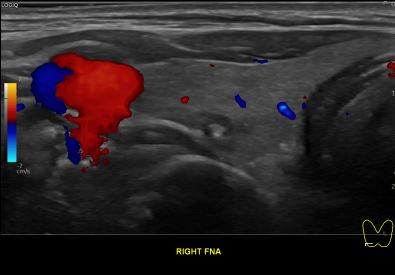

상기환자 외부건진 이상소견으로 내원하신 60대 중반 여성분으로

의심스러운 갑상선 우엽 세포검사후 갑상선암으로 진단되었습니다